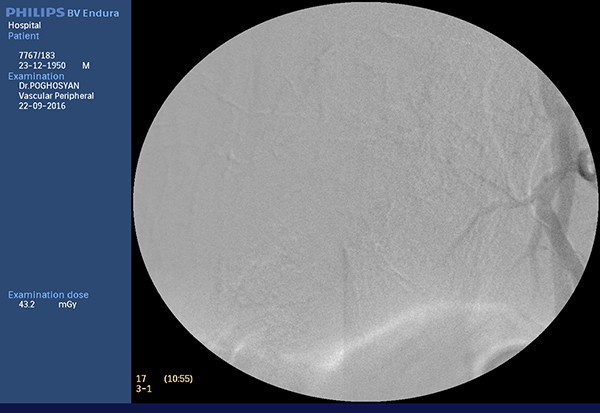

Առկա մուգ գույնով ներկված հատվածները քիմիապրեպարատի և էմբոլիզացնող նյութի կուտակումն է ուռուցքային հյուսվածքում Դեպի ուռուցք գնացող անոթները բացակայում են

էնդովասկուլյար վիրաբույժ Պողոսյան Տ.Ս.